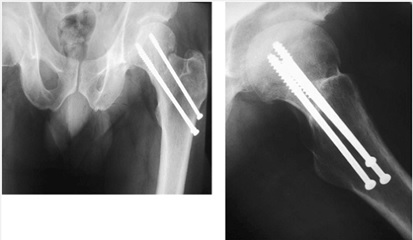

در درمان جراحي اين شكستگيها در سنوات گذشته وسايل مختلفي امتحان شده است و نهايتاً امروزه از وسيلهاي به نام پيج كمپرشن ديناميك هيپ (DHS) استفاده ميشود.

عكس و راديوگرافي نشانده پيچ ديناميك هيپ (DHS) براي فيكساسيون شكستگي اينترتروك است